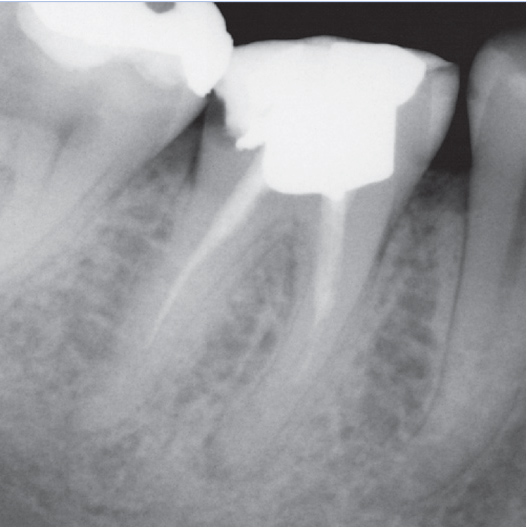

Before

After

Before Root Canal treatment

After Root Canal treatment